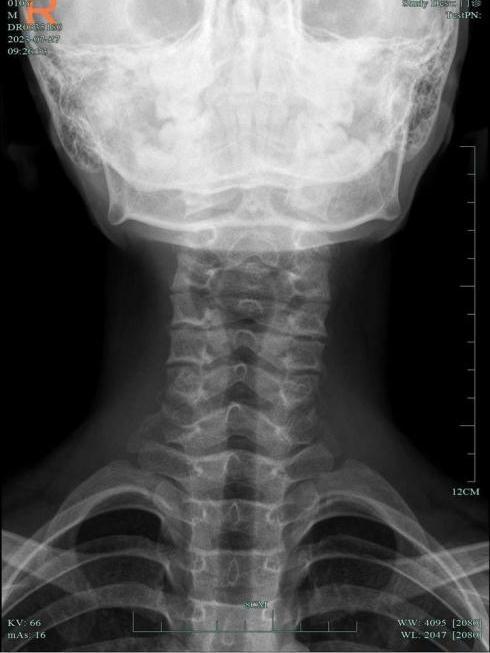

王主任查看小杰的頸部DR片驚訝地吐出四個字:一塌糊涂!

小杰頸椎病變嚴重,小關節錯位,頸椎反弓。明明才10歲,頸椎已經跟30歲的人一樣,老化程度甚至超過不少接診的成年人。